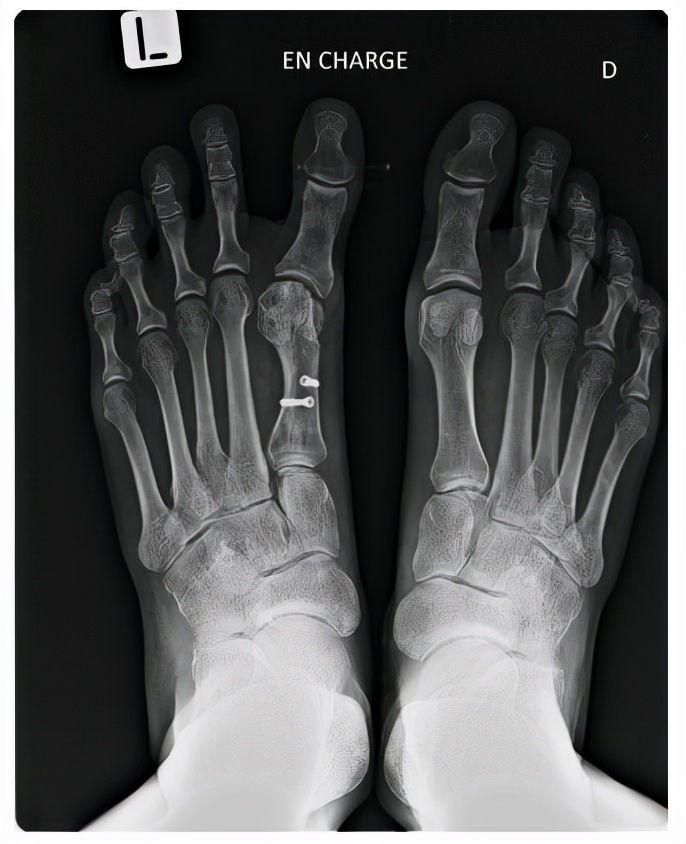

术后即出现拇指内翻,说明内侧关节囊重叠缝合过度,跖骨力线不良引起,通常是关节囊处过度紧缩或是外侧过度松解的结果,可采取踇趾向外位加强包扎8周的方法进行纠正。如果拇内翻仍存在,可能是IMA纠正过度,需再次行跖骨截骨术或跖楔关节融合术,需要尽早做,以减少软组织挛缩导致的相关问题。